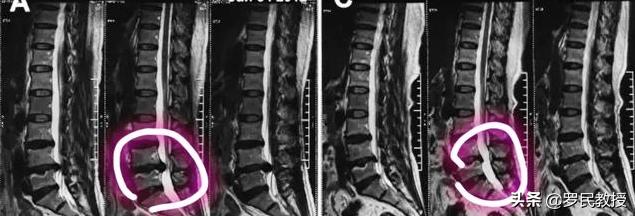

腰椎ヘルニアの患者さんの口に出てくるヘルニアとは、椎間板の中にある「髄核」のことを指し、それ自体は椎間板に大きな影響を与えるものではありませんが、突出した後は周囲の神経組織に圧迫や刺激を与え、炎症や腫れを生じ、様々な症状を引き起こすことになります。椎間板ヘルニアの拡大は(症状とは無関係に)症状の悪化を意味し、椎間板ヘルニアが大きくなってしまっては、すべての患者さんを治療する意味がなくなってしまうので、椎間板ヘルニアの拡大(髄核のさらなる突出)は存在するが、あくまでも可能性の一つに過ぎないということを理解しなければなりません。

まず、腰椎椎間板ヘルニアの治療において、確かに反転は可能であり、そのような症例は稀ではあるが存在すること、しかし患者の大半は軽症(主に膨隆型)であること、私はこれまでのキャリアでそれを目にしてきたこと、しかし、チャンスを逃し(タイムリーに治療を進めず)、かえって治療の最適な時期を遅らせてしまう人が多いかもしれないので、あまり人々の期待を持たせたくないというコンセプトから肯定しておきます。

答えはイエスですが、すべての患者に当てはまるわけではありません。腰椎椎間ヘルニアの退縮に関しては、ヘルニアの縮小(退縮、吸収)、ヘルニアの大きさは変わらず徐々に石灰化、ヘルニアの拡大、ヘルニアの脱出(椎間板の線維性環の破裂、後縦靭帯の破裂)などがあります。